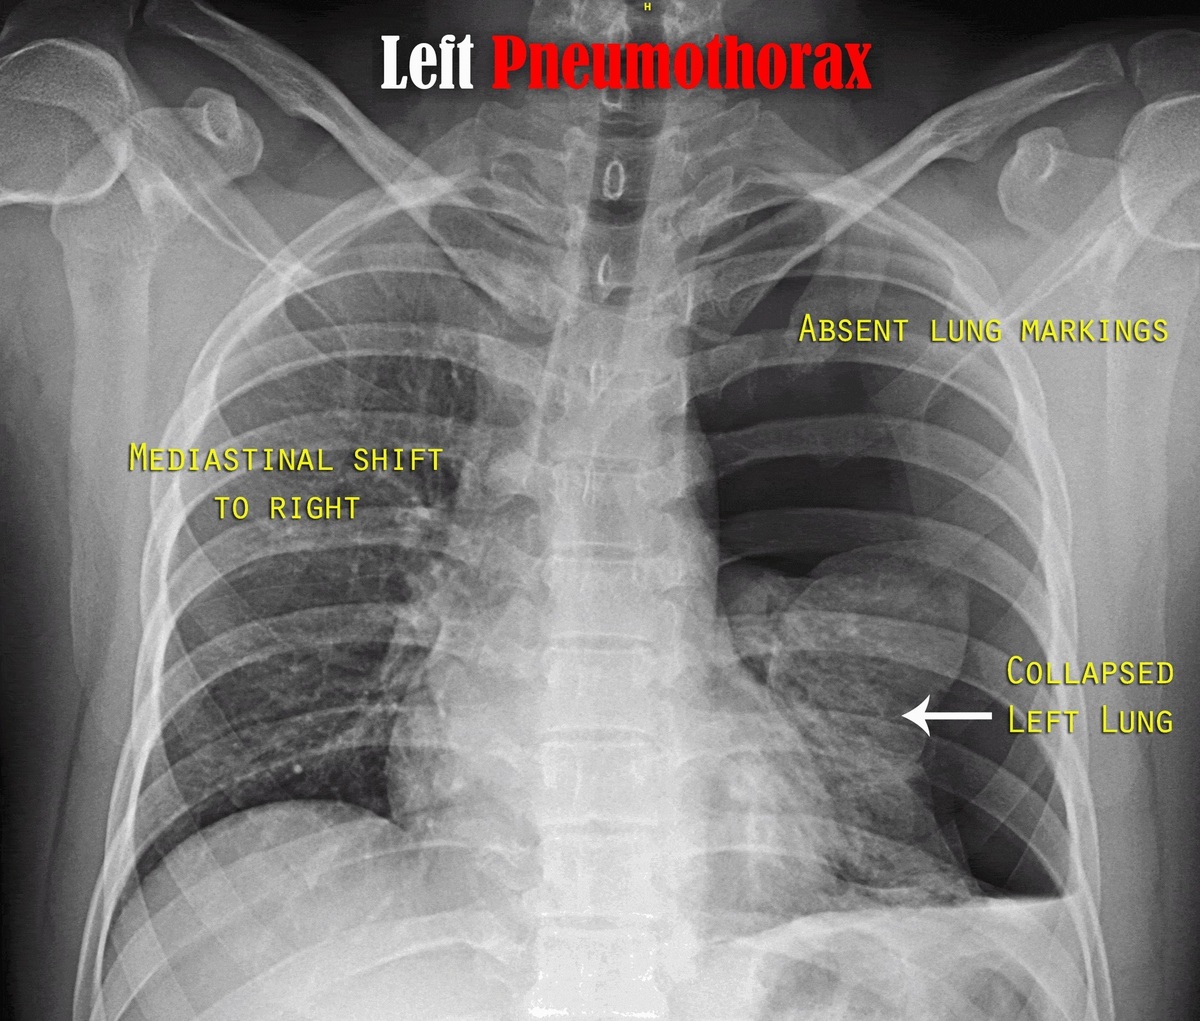

Q

what does this CXR show?

A

tension pneumothorax

- mediastinal shift to right

- absent lung markings

How well did you know this?